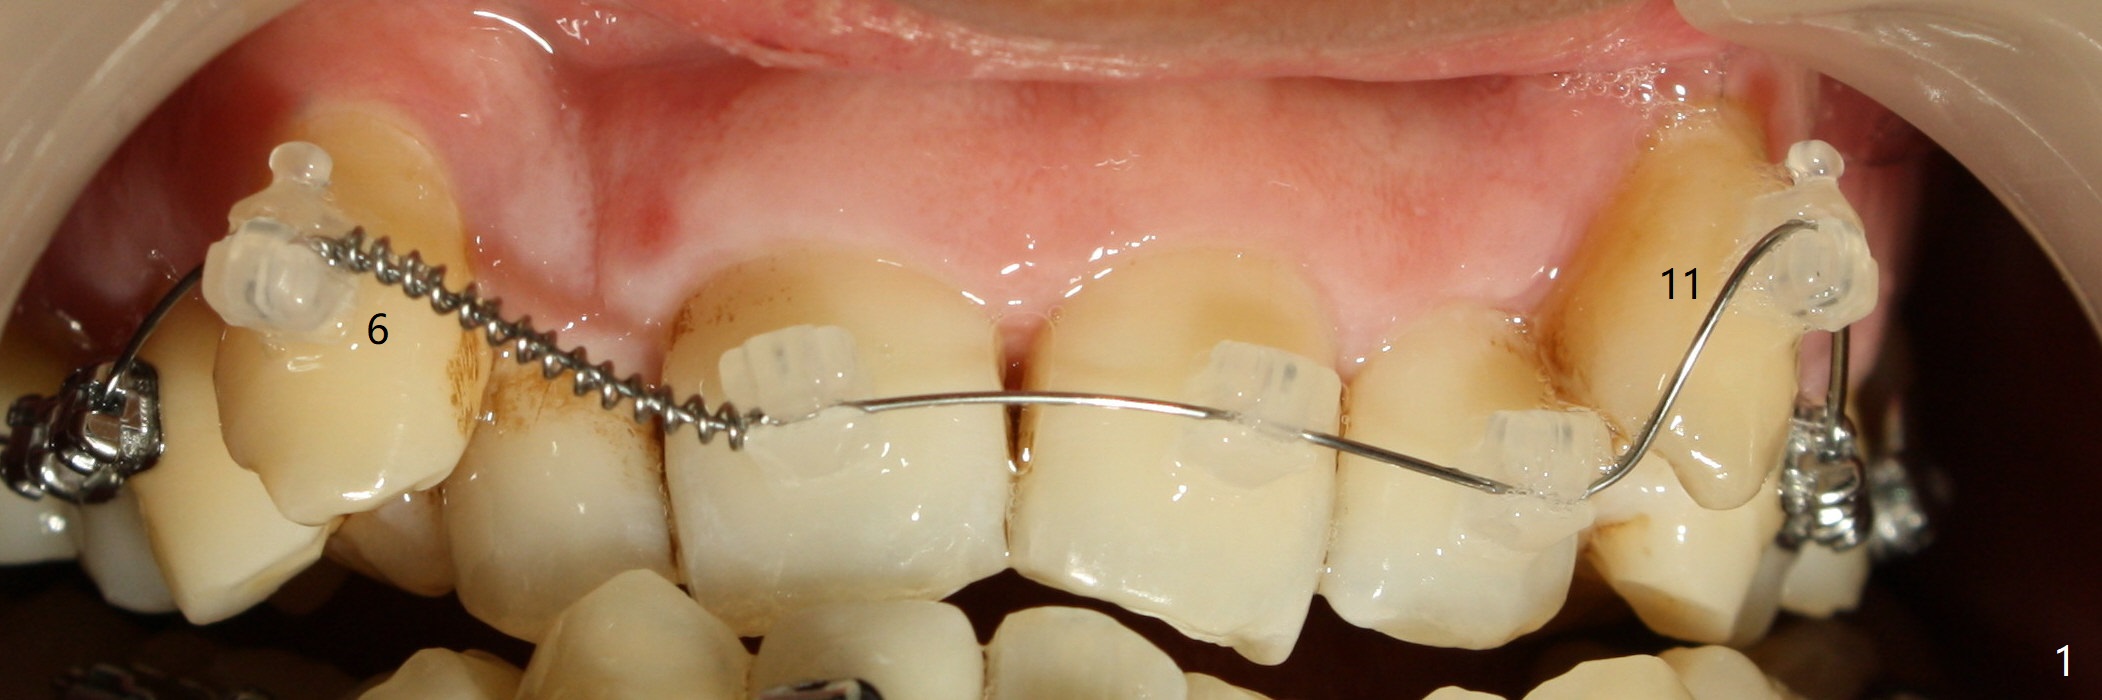

A 45-year-old man had severe malocclusion and chose non-extraction orthodontic treatment (Fig.1 (2012)). Five years later, the tooth #11 discolors (Fig.3, as compared to #6 in Fig.2). Immediately after RCT (Fig.4,5), the affected tooth has sudden change in shade (Fig.6). Two weeks later there is rebound in shade (Fig.7). The latter improves after two rounds of chair-side internal bleaching with 35% Hydrogen Peroxide for 20 minutes and build-up with the lightest shade composite (Fig.8). For optimum, place the bleach gel in the pulpal chamber and close the access with Cavit for a few days. In fact the latter is unnecessary. The treated tooth looks as normal as the tooth on the other side 1 year 10 months post whitening (Fig.9). PARL reduces 3 years post RCT (Fig.10 <, as compared to Fig.5).